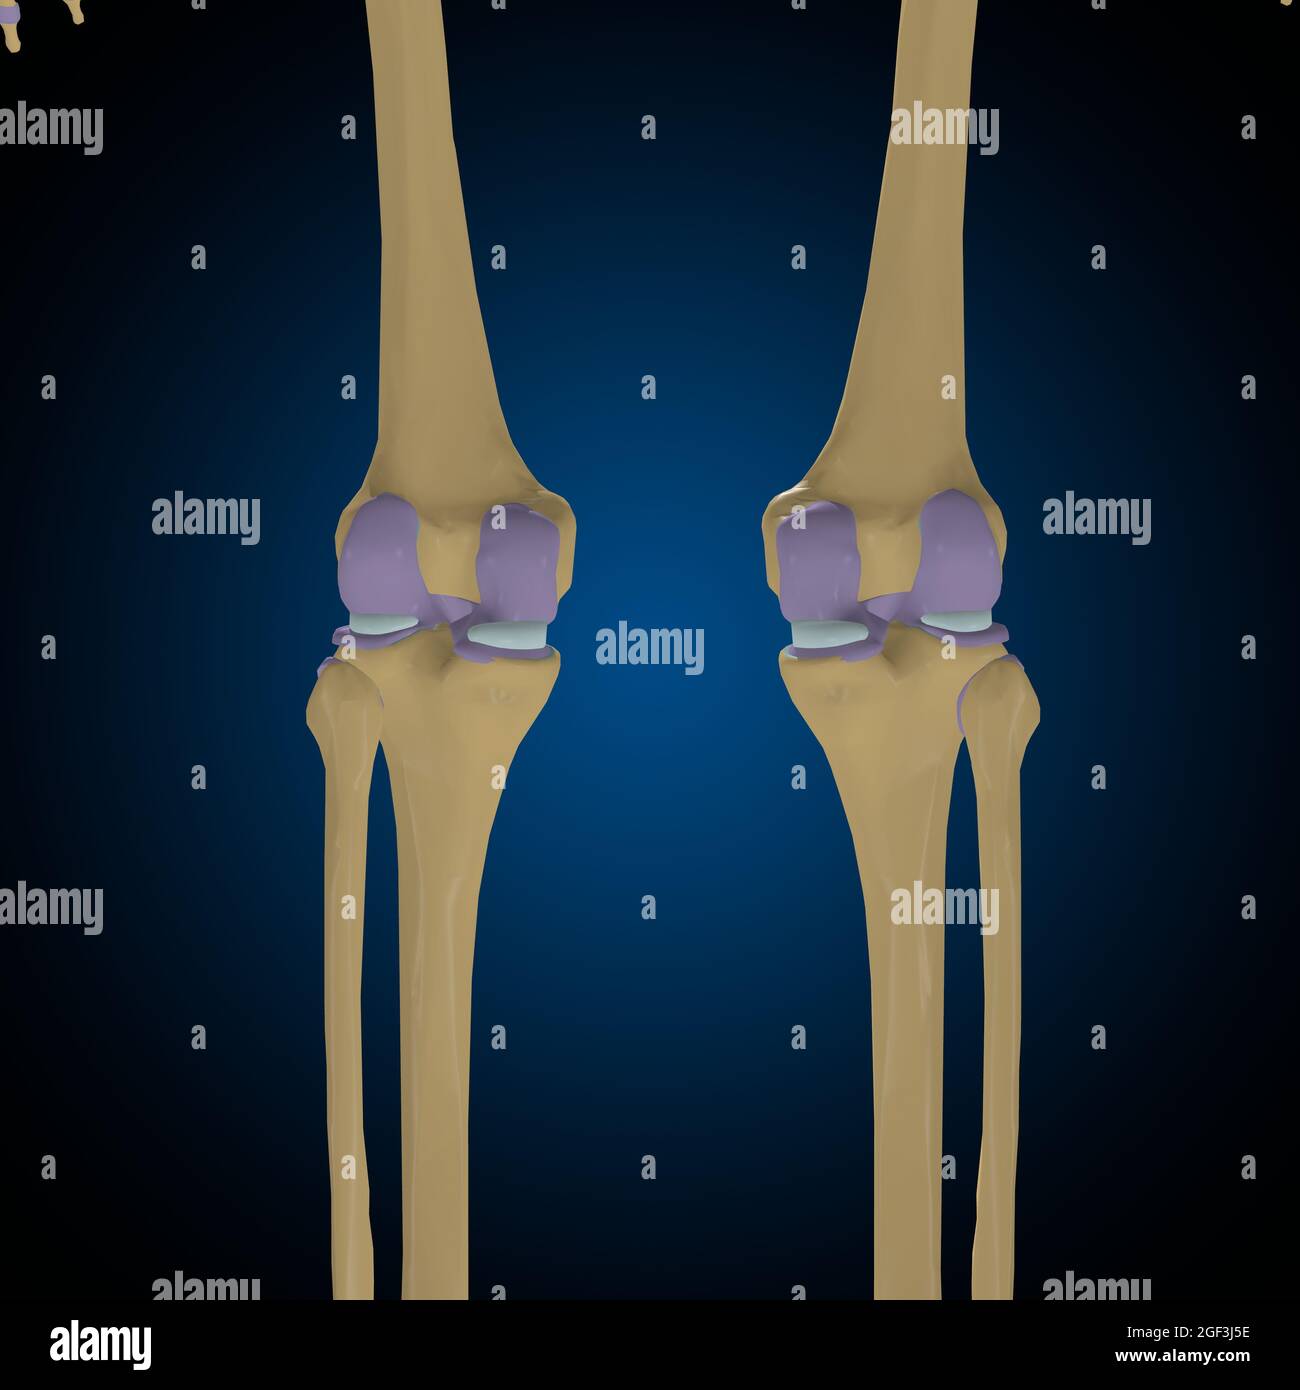

Articular capsule Anatomy For Medical Concept 3D Illustration Stock Photohttps://www.alamy.com/image-license-details/?v=1https://www.alamy.com/articular-capsule-anatomy-for-medical-concept-3d-illustration-image439559253.html

Articular capsule Anatomy For Medical Concept 3D Illustration Stock Photohttps://www.alamy.com/image-license-details/?v=1https://www.alamy.com/articular-capsule-anatomy-for-medical-concept-3d-illustration-image439559253.htmlRF2GF3J8N–Articular capsule Anatomy For Medical Concept 3D Illustration

Articular capsule Anatomy For Medical Concept 3D Illustration Stock Photohttps://www.alamy.com/image-license-details/?v=1https://www.alamy.com/articular-capsule-anatomy-for-medical-concept-3d-illustration-image439559233.html

Articular capsule Anatomy For Medical Concept 3D Illustration Stock Photohttps://www.alamy.com/image-license-details/?v=1https://www.alamy.com/articular-capsule-anatomy-for-medical-concept-3d-illustration-image439559233.htmlRF2GF3J81–Articular capsule Anatomy For Medical Concept 3D Illustration

Articular capsule Anatomy For Medical Concept 3D Illustration Stock Photohttps://www.alamy.com/image-license-details/?v=1https://www.alamy.com/articular-capsule-anatomy-for-medical-concept-3d-illustration-image439559176.html

Articular capsule Anatomy For Medical Concept 3D Illustration Stock Photohttps://www.alamy.com/image-license-details/?v=1https://www.alamy.com/articular-capsule-anatomy-for-medical-concept-3d-illustration-image439559176.htmlRF2GF3J60–Articular capsule Anatomy For Medical Concept 3D Illustration

Articular capsule Anatomy For Medical Concept 3D Illustration Stock Photohttps://www.alamy.com/image-license-details/?v=1https://www.alamy.com/articular-capsule-anatomy-for-medical-concept-3d-illustration-image439559162.html

Articular capsule Anatomy For Medical Concept 3D Illustration Stock Photohttps://www.alamy.com/image-license-details/?v=1https://www.alamy.com/articular-capsule-anatomy-for-medical-concept-3d-illustration-image439559162.htmlRF2GF3J5E–Articular capsule Anatomy For Medical Concept 3D Illustration

Articular capsule Anatomy For Medical Concept 3D Illustration Stock Photohttps://www.alamy.com/image-license-details/?v=1https://www.alamy.com/articular-capsule-anatomy-for-medical-concept-3d-illustration-image439559178.html

Articular capsule Anatomy For Medical Concept 3D Illustration Stock Photohttps://www.alamy.com/image-license-details/?v=1https://www.alamy.com/articular-capsule-anatomy-for-medical-concept-3d-illustration-image439559178.htmlRF2GF3J62–Articular capsule Anatomy For Medical Concept 3D Illustration

Articular capsule Anatomy For Medical Concept 3D Illustration Stock Photohttps://www.alamy.com/image-license-details/?v=1https://www.alamy.com/articular-capsule-anatomy-for-medical-concept-3d-illustration-image439559254.html

Articular capsule Anatomy For Medical Concept 3D Illustration Stock Photohttps://www.alamy.com/image-license-details/?v=1https://www.alamy.com/articular-capsule-anatomy-for-medical-concept-3d-illustration-image439559254.htmlRF2GF3J8P–Articular capsule Anatomy For Medical Concept 3D Illustration